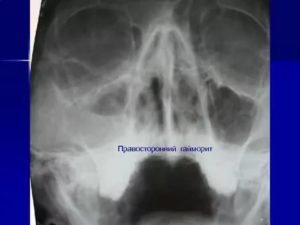

При такой форме поражается только правая часть верхнечелюстной пазухи. Все болевые ощущения можно наблюдать только с правой стороны. Процесс воспаления может носить как острый, так и хронический характер. От того, на какой стадии находится заболевание, определяются и методы терапии: хирургическое или консервативное вмешательство.

Симптомы правостороннего катарального гайморита

- выделения из правой ноздри и ее заложенность;

- повышение температуры;

- отечность правой стороны;

- сильные правосторонние боли.

Локализацию болезни проще всего обнаружить на рентгеновском снимке. Патология отображается на нем в виде темных пятен различного объема.